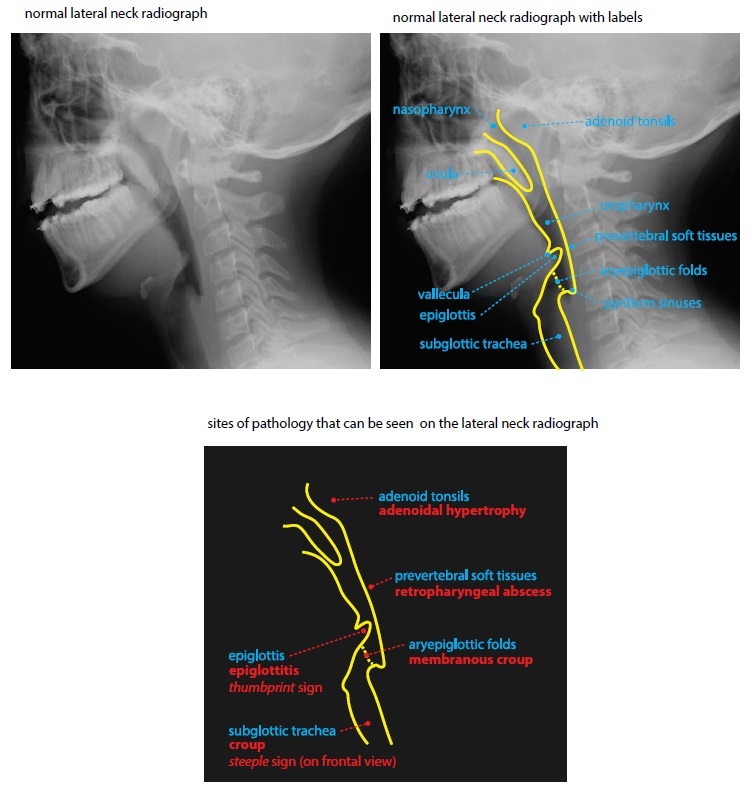

Normal lateral neck radiograph

The classic radiographic findings of epiglottitis are thickening of the epiglottis seen on the lateral view (the thumbprint sign) in conjunction with thickening of the aryepiglottic folds.

The steeple sign is seen on the frontal view and represents loss of the normal shouldering of the subglottic trachea. There may be “ballooning” of the hypopharynx on the lateral view.

Retropharyngeal abscess is purulent infection of the retropharyngeal space and is one of the more common causes of nontraumatic prevertebral soft tissue swelling in children.

Retropharyngeal pseudothickening can be seen if a radiograph is obtained in neck flexion.

A retropharyngeal abscess rarely presents with air in the retropharyngeal tissues unless a foreing body has perforated the esophagus.

On imaging, intraluminal mebranes may be visible in the subglottic and cervical trachea.